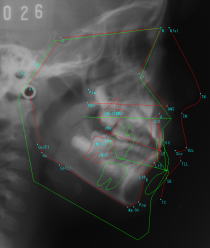

ƒZƒtƒ@ƒ•ªÍ‚Ŭ’·‚Ì—\‘ª‚ð‚µ‚Ü‚·BiŒ©Ï‚à‚è–³—¿j